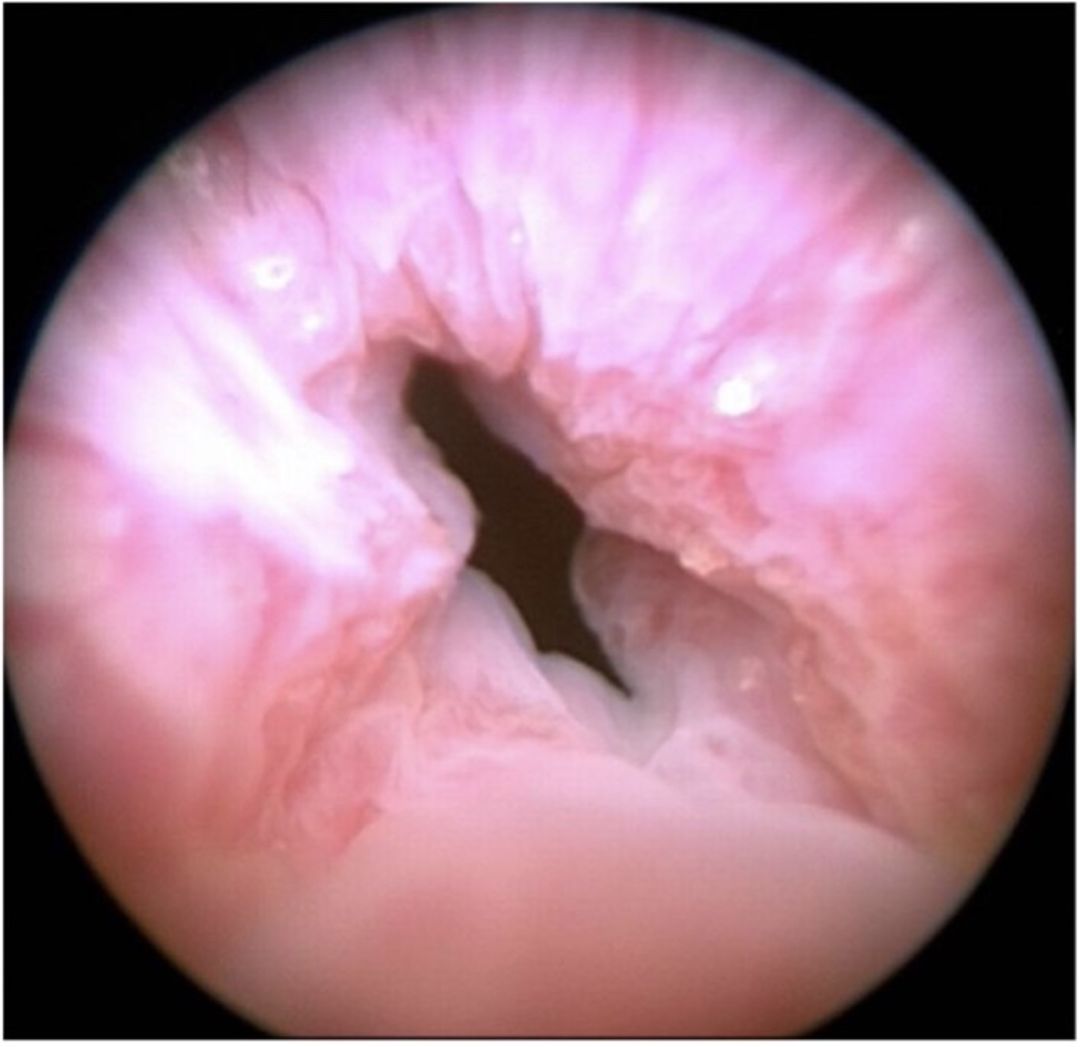

Figure 1 pre optilume